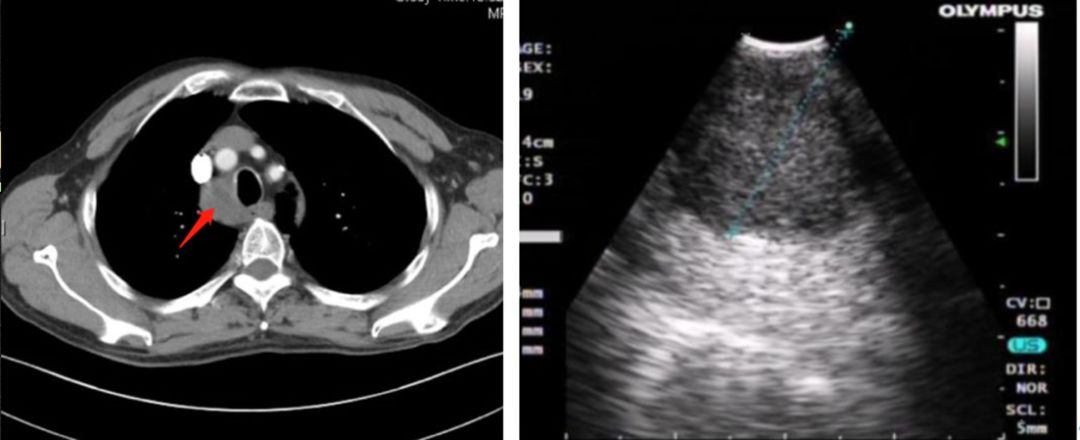

图1 增强CT提示纵隔淋巴结肿大(左);经气道内超声测量纵隔肿大淋巴结(右)

患者为73岁老年男性,因纵隔淋巴结肿大(2R)而入院;既往有脑血管病及长期抽烟的病史。临床检测外周血癌胚抗原(CEA)明显升高。胸部增强CT显示右侧气管旁淋巴结(2R)明显肿大,双侧肺内未见明显病灶。为进一步明确诊断,患者在全身麻醉下经喉罩置入支气管镜进行观察,然后行超声支气管镜检查,超声镜下可见2R淋巴结明显肿大,直径2.0×3.0cm,内部回声较均匀,边界清晰,包膜完整(图1右)。在超声内镜下使用超声活检针于2R淋巴穿刺活检4针(图2),取材满意,标本分别送检细胞学和组织病理学。术后病理回报:可见恶性肿瘤细胞,倾向于腺癌(图3)。为患者下一步治疗指明了方向。